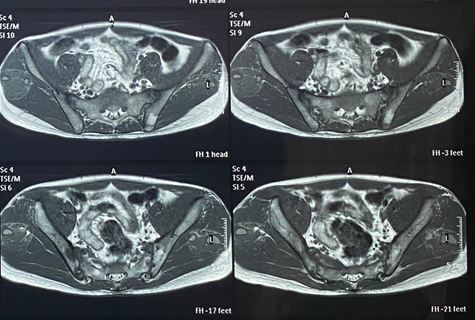

Bệnh viêm cột sống dính khớp là một dạng viêm khớp mạn tính gặp ở hai giới nam và nữ trẻ tuổi nhưng nam gặp nhiều hơn nữ. Bệnh nếu không được điều trị đúng cách và đúng thời điểm có thể để lại nhiều di chứng nặng nề như đau đớn, biến dạng, cong